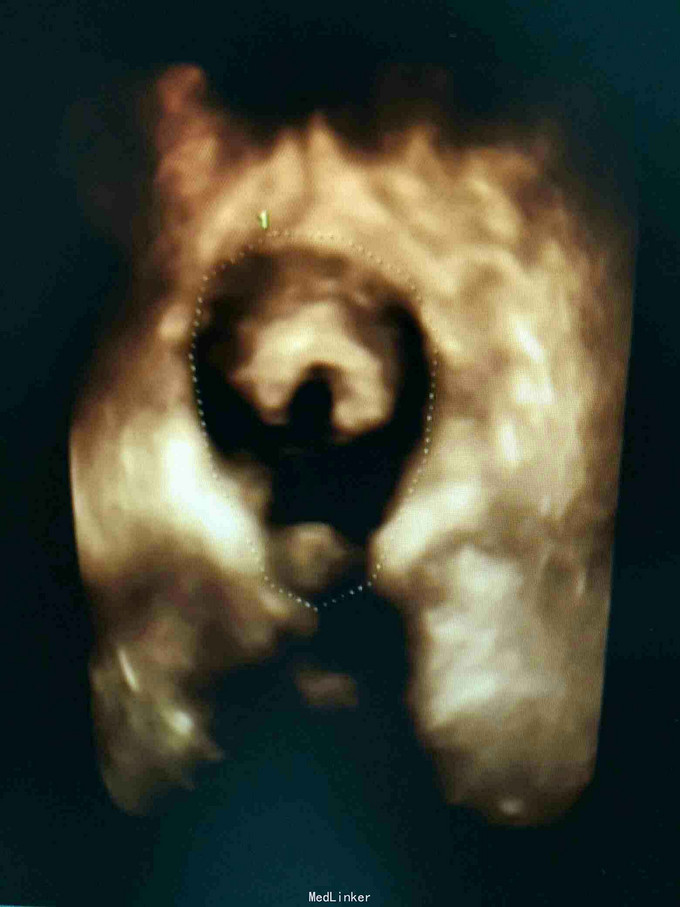

查体:双肾区无红肿、隆起,无叩痛,双侧肋脊点、肋腰点无压痛。尿道口可见大小约3mm息肉,未见盆腔脏器脱出。 辅查:2015-12-8清远市中医院IVP未见明显异常;胸片提示主动脉硬化;泌尿系B超未见异常;膀胱镜检提示膀胱憩室,左右侧壁各1个,分别约2*3cm、3*4cm;尿道口息肉。